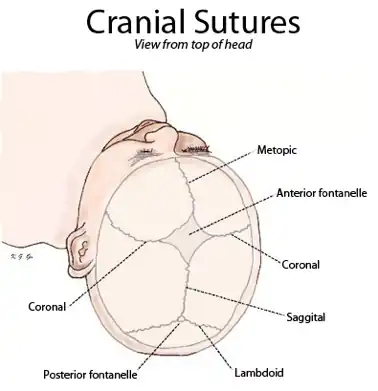

- Sutures: The skull bones are connected by fibrous joints called sutures.[1] In fetal skulls, the sutures are wide to allow slight movement during birth. They later become rigid (synarthrodial).

A suture is a type of fibrous joint that is only found in the skull (cranial suture). The bones are bound together by Sharpey's fibres. A tiny amount of movement is permitted at sutures, which contributes to the compliance and elasticity of the skull. These joints are synarthroses.[1] It is normal for many of the bones of the skull to remain unfused at birth. The fusion of the skull's bones before birth is known as craniosynostosis. The term "fontanelle" is used to describe the resulting "soft spots". The relative positions of the bones continue to change during the life of the adult (though less rapidly), which can provide useful information in forensics and archaeology. In old age, cranial sutures may ossify (turn to bone) completely.[3] The joints between the teeth and jaws (gomphoses) and the joint between the mandible and the cranium, the temporomandibular joint, form the only non-sutured joints in the skull.

Visible from the front or above

- Frontal suture / Metopic suture – between the two frontal bones, prior to the fusion of the two into a single bone

- Sagittal suture – along the midline, between parietal bones

Top view of cranial suture.

Top view of cranial suture.